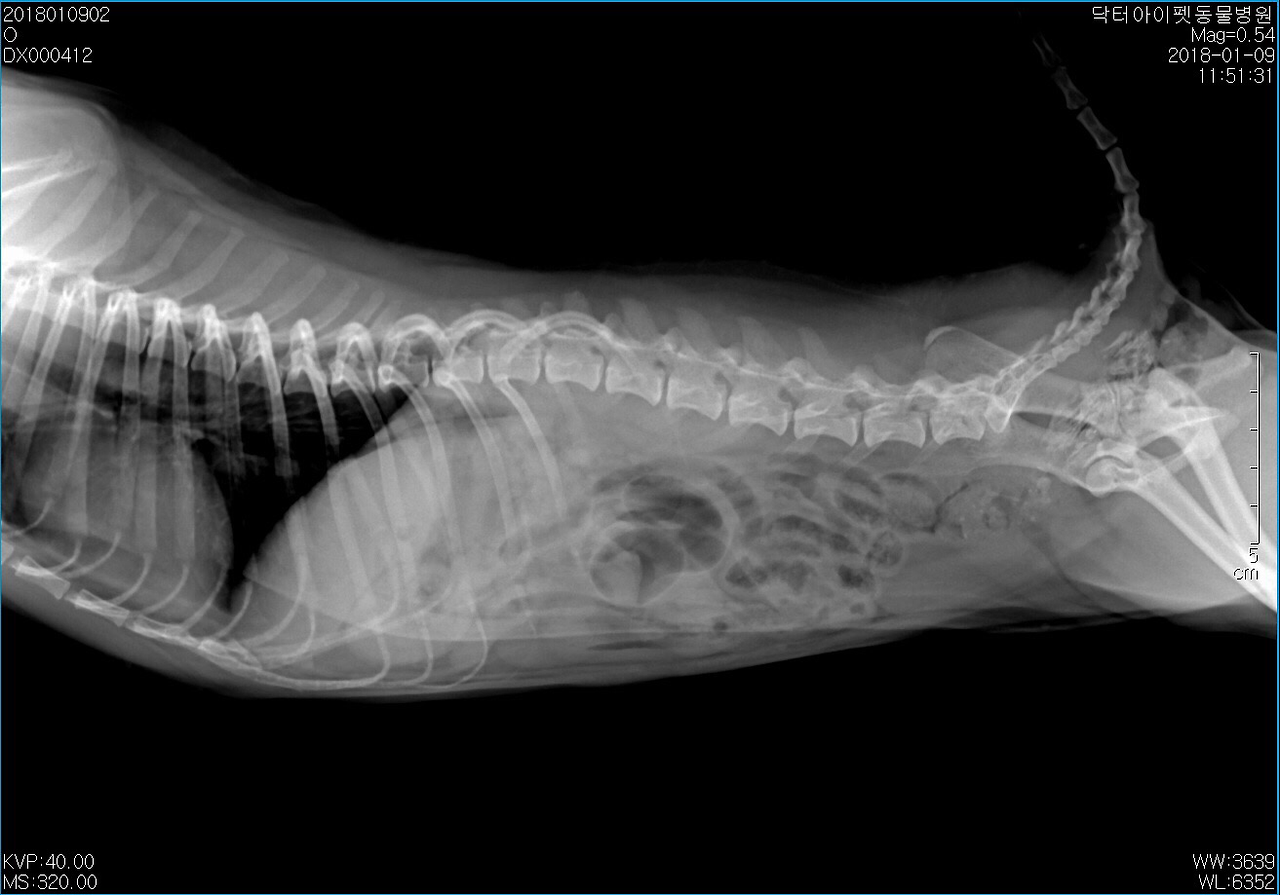

엑스레이를 찍어봤다. 위 한 가득 치킨 뼈가 차있었다. 일반적인 케이스라면 수술을 우선적으로 고려했을 거다. 다행스럽게도 띠띠는 침을 많이 흘리거나 출혈성 구토, 혈변 등의 증상이 없었다. 절대 금식을 당부하고 3일 통원치료를 계획했다. 72시간 정도 경과하면 대부분 섭취한 음식물은 소화되기 따름이다. 기대한 대로 대부분 소화되어 대변으로 배출되었다.

통원 1일, 2일, 3일차 방사선 사진. 다행이었다. 뼈는 모두 소화되고 배출되었다.